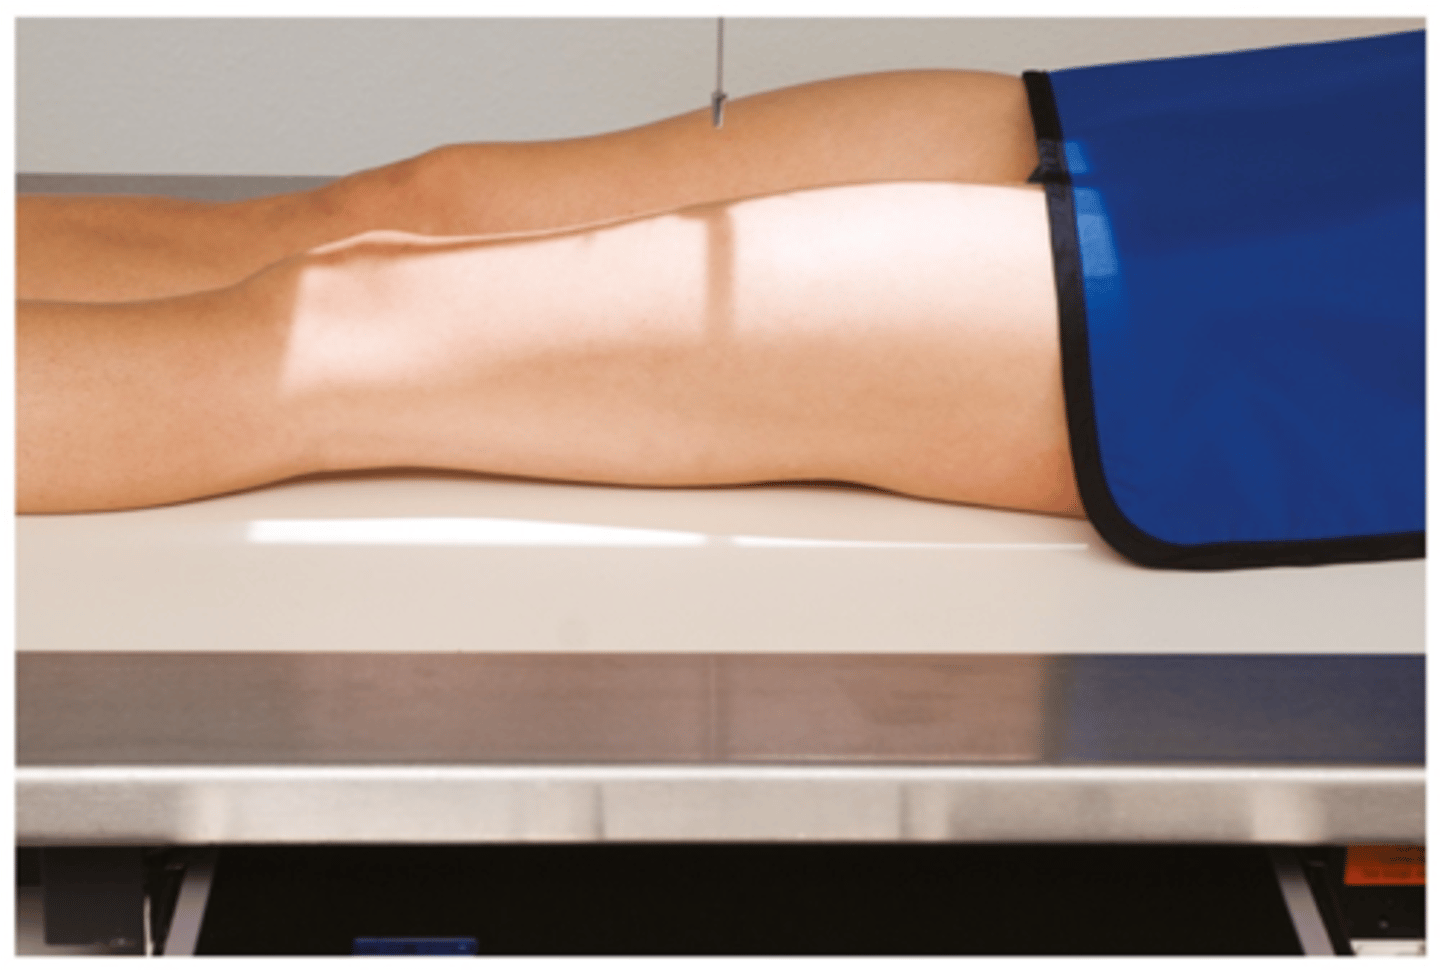

Describe, in detail, how a PATIENT should be positioned for an AP FEMUR projection.

1. Patient lies supine on the x-ray couch and the legs are extended.

2. Posterior aspect of the leg is in contact with the x-ray couch.

3. The IR is placed in the bucky. Make sure that the x-ray tube is locked in with the bucky system.

4. The leg is medially rotated to centralise the patella. The condyles should be equidistant to the IR.

If it is not possible to get both the hip and knee joint on the same IR, then this exposure should be hip down and then a second IR to do an 'out of bucky' knee up exposure.